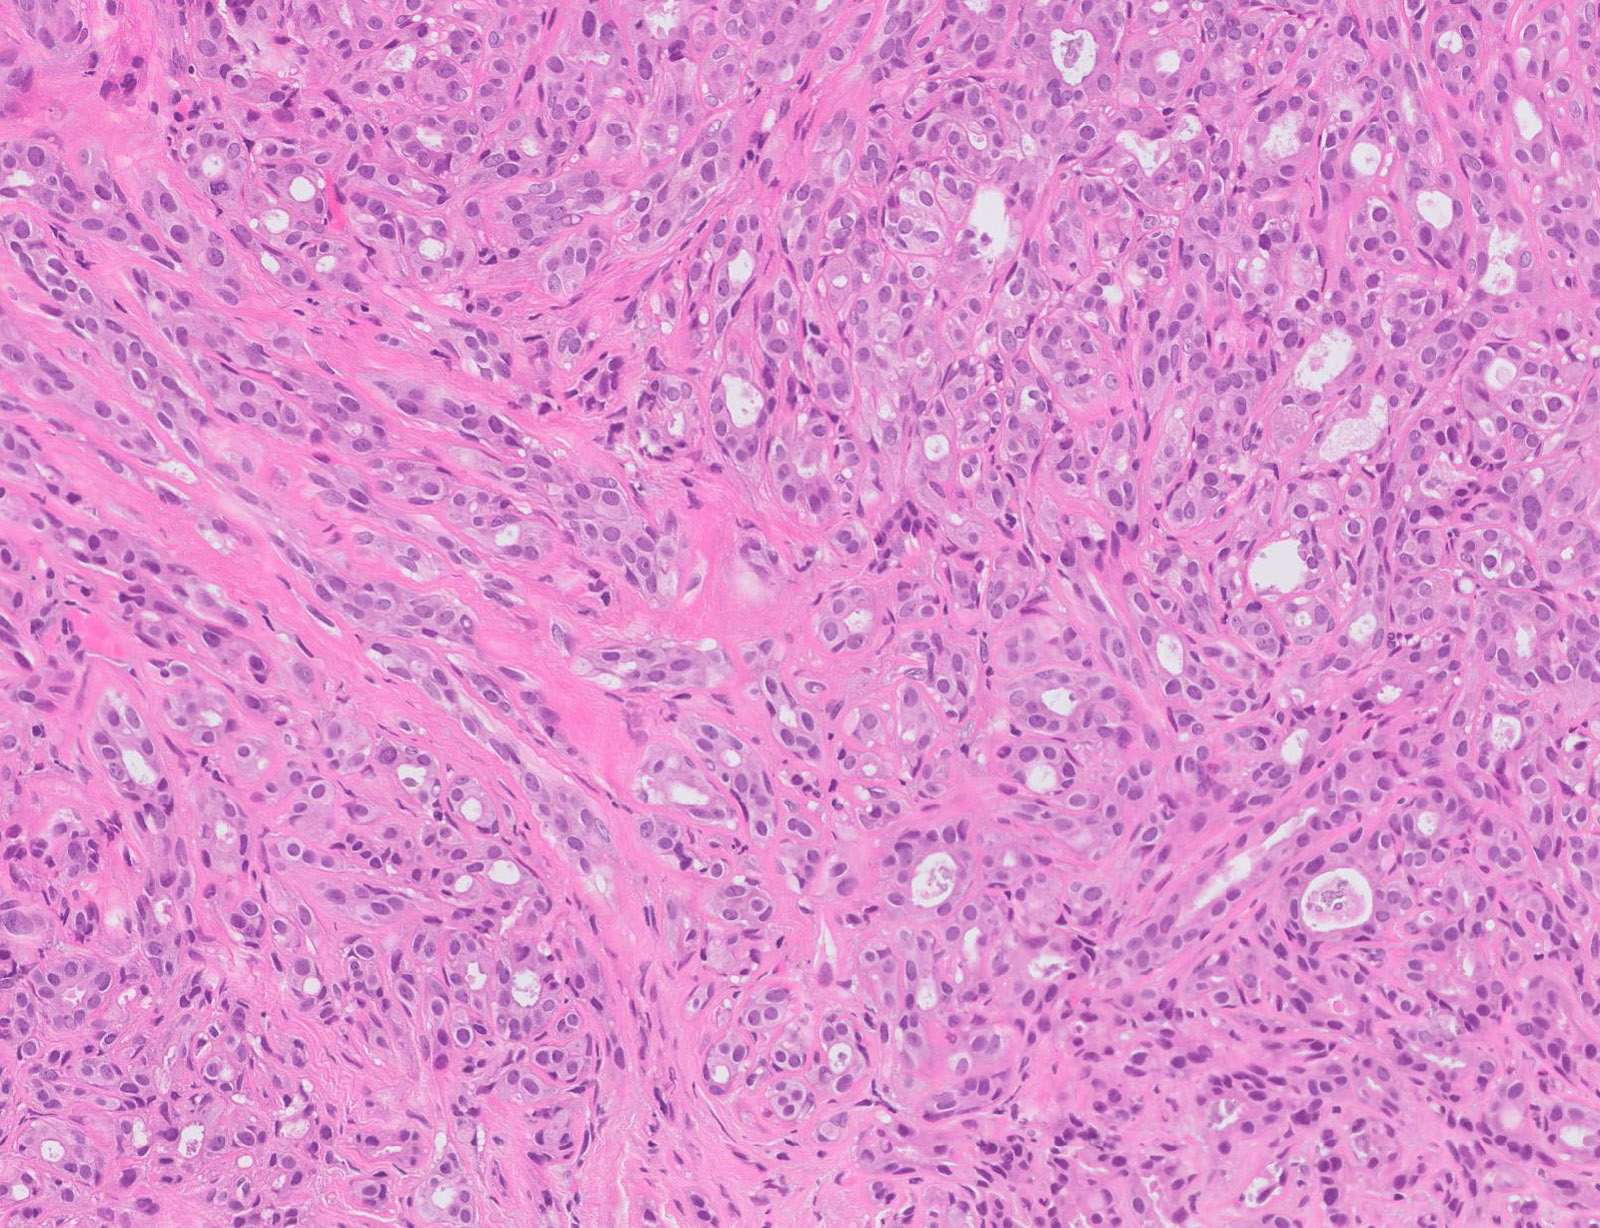

Microscopic (histologic) description

- Well defined borders

- Sparse fibrovascular stroma intervening tubules

- Small, uniform, closely packed round tubules (Clin Med Insights Pathol 2018;11:1179555718757499)

- Lined by an inner layer of luminal epithelial cells and an outer layer of myoepithelial cells

- Rare mild atypia and mitotic figures does not exclude diagnosis

- Occasional luminal eosinophilic secretion

- Lined by an inner layer of luminal epithelial cells and an outer layer of myoepithelial cells

Microscopic (histologic) images

Contributed by Joshua J.X. Li, M.B.Ch.B. and Gary M. Tse, M.B.B.S.